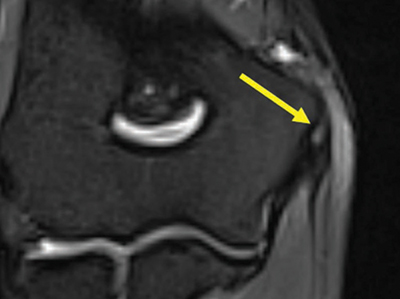

Figure 4

Coronal fat-saturated T2-weighted image through the medial flexor origin with an intratendinous T2-hyperintense signal, score 2.

Multiple linear T2-hyperintensities were seen distally in the triceps tendon parallel to its fibers among all patients (Figure 2). The common flexor tendon showed signal alterations in 8% of patients; 4% of them had an increased signal around the tendon (score 1) (Figures 3) and 4 % of the patients had an increased signal within the tendon (score 2) (Figure 4).

The common flexor tendon was the tendon in which alterations of signal were most frequently observed (8%). Half of these abnormal signals occurred in the tendon itself, mimicking a tendinopathy, similar to the findings in the literature (3%) [11].